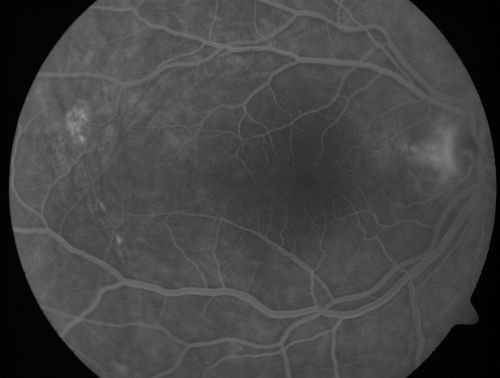

Nanopthalmous (Microphthalmous) Chorioretinal Folds and Choroidal Thickening Both Eyes

67-year-old woman with microphthalmos/nanophthalmos  Her vision has gradually been getting a little bit worse, especially in the right eye.  Also the anterior chamber is getting crowded and there is concern about the need for cataract surgery.  She has one sister and one cousin who also have nanophthalmos.

VISUAL ACUITY:  OD 20/50,  OS 20/80.